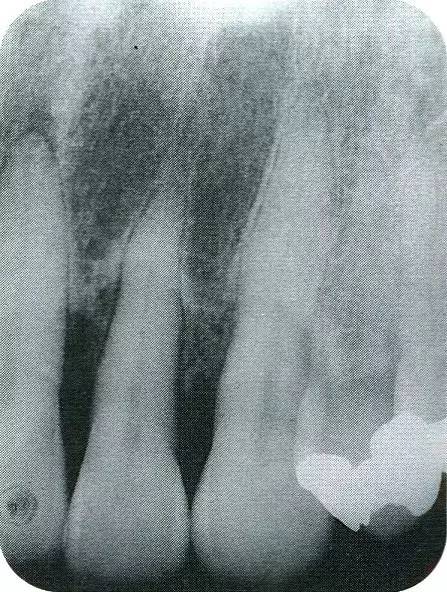

640.webp (6).jpg

▲圖7-7  術(shù)前,術(shù)后的x片。確認(rèn)出現(xiàn)骨再生,牙槽嵴硬線。